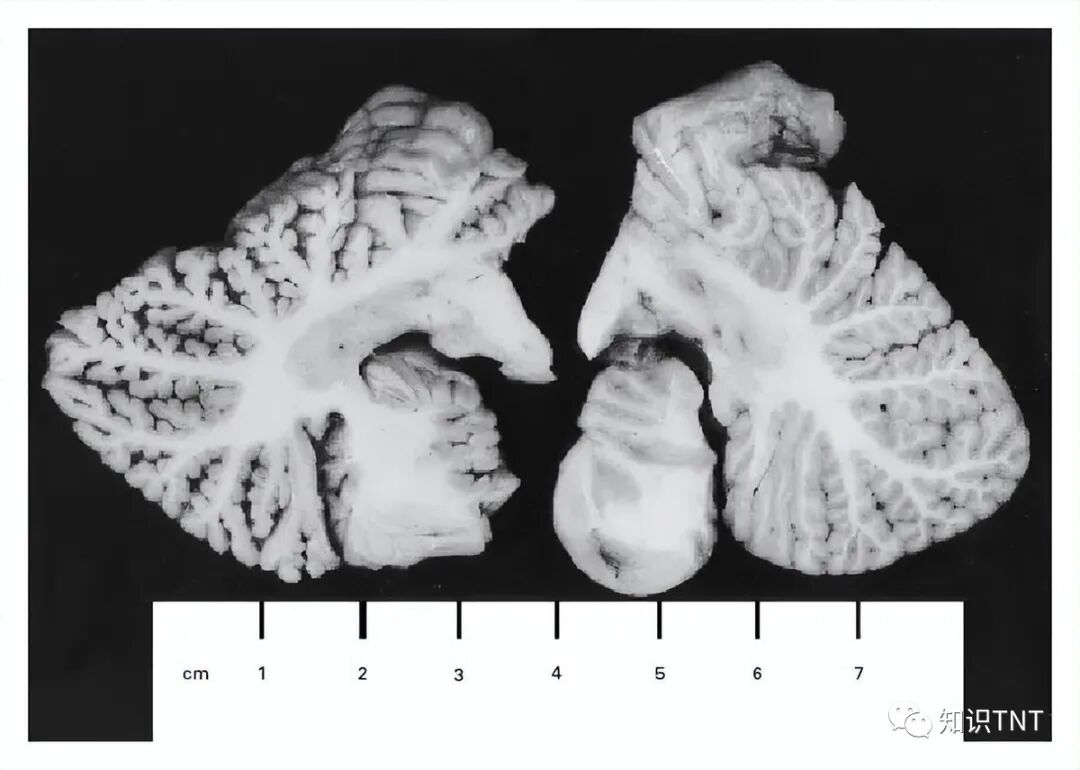

海伦的尸检结果显示,她的听觉、视觉皮层都出现了严重的胶质化。大脑皮层薄到只剩下3毫米,脑内神经元大量丢失,无论是种类还是数量,都远远不足刚出生小婴儿的大脑水平。

同时,前额叶、视觉皮层和肝脾脏的汞含量依然超标近4000倍,是普通尸体检测样本的1200倍。